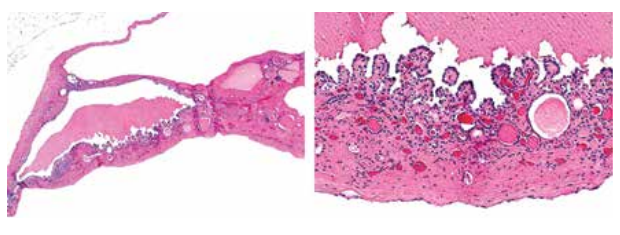

Как диагностировать кисту почки?

Чаще всего, киста почки выявляется при помощи УЗИ во время профилактического обследования или обследования по поводу другого заболевания. Золотым стандартом диагностики, позволяющим не только выявить кисту почки, но и определить ее категорию по классификации Босниак, а также визуализировать ее хирургическую топографию (что крайне важно для планирования оперативного вмешательства) являются компьютерная томография или магнитно-резонансная томография внутривенным контрастированием.